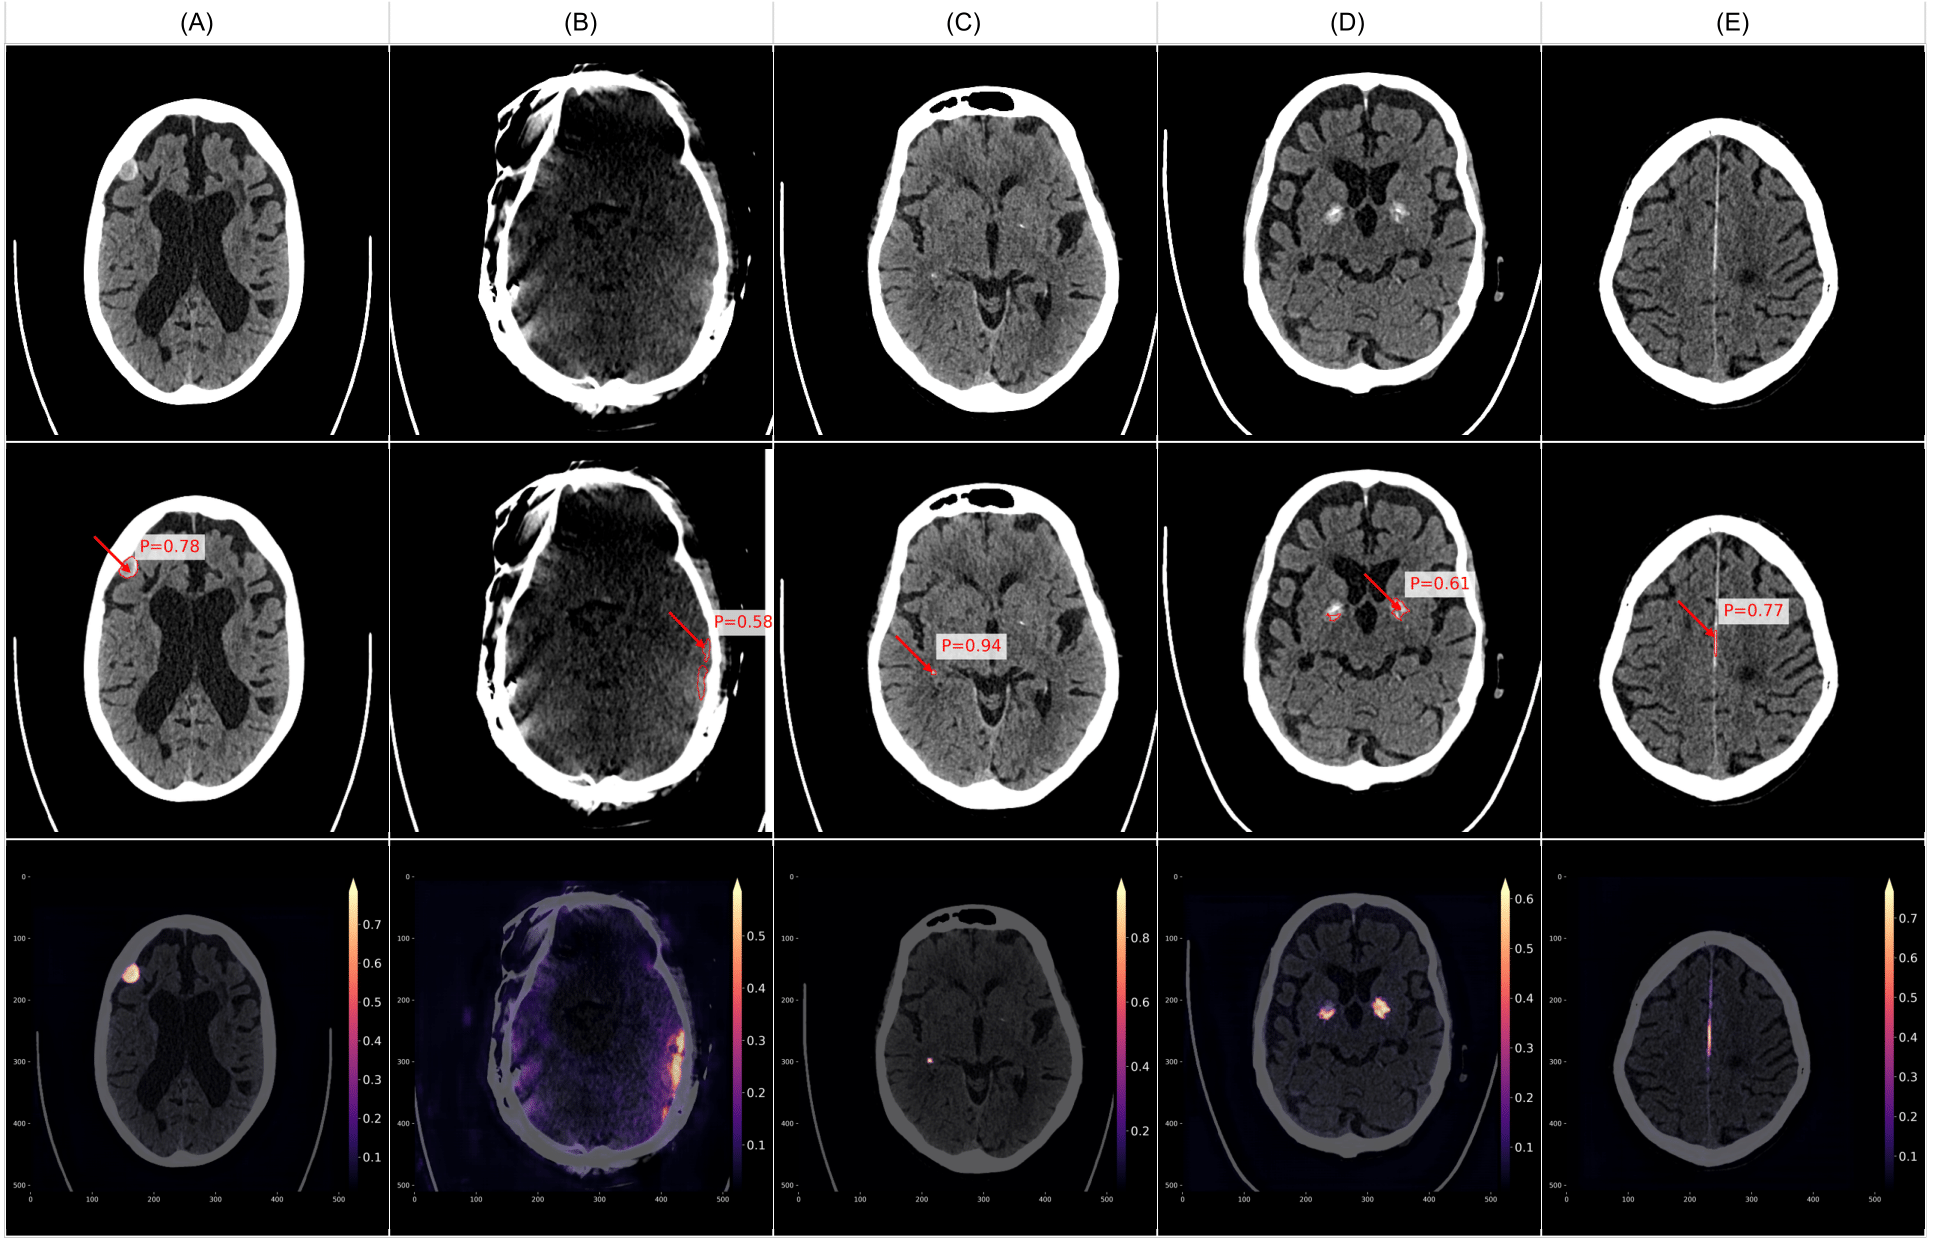

Figure 9 presents examples of true positive cases where VIOLA-AI successfully detected intracranial hemorrhage in CT scans. Specifically, (A) and (B) illustrate smaller ICH, (C) depicts acute SDH, (D) shows a combination of SAH, IPH, and IVH, and (E) highlights both acute SDH and SAH. These images showcase the model’s capability to accurately detect a range of hemorrhage types and volumes, underscoring its high sensitivity and precision in identifying positive cases.

Figure 10 illustrates examples of false positive cases, where VIOLA-AI incorrectly identified ICH in CT scans that did not contain any bleeds. These misclassifications often arise because some bleed-like features closely resemble non-hemorrhagic structures. Contributing factors include imaging artifacts (e.g., B: motion artifacts) and the model’s heightened sensitivity to certain high-density regions, such as various calcifications. Examples include A: a partly calcified meningioma, C: choroid plexus calcifications, D: basal ganglia calcifications, and E: falx and dura calcifications. Analyzing these false positives is crucial for refining the model to better distinguish between true hemorrhages and similar-looking non-bleed findings, thereby improving overall accuracy.